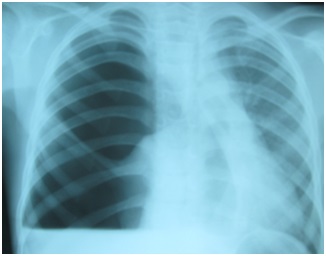

63

bronş ağzı tümörle tam tıkalı. PA Akciğer grafisindeki radyografik bulgu nedir?

a)

Diyafram

evantrasyonu

b)

Atelektazi

c)

Plevral

sıvı

d)

Kitle

e)

Pnömonik

infiltrasyon